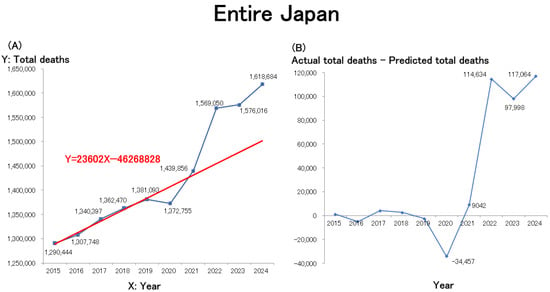

Since the onset of the COVID-19 pandemic, Japan has experienced a significant rise in mortality, with excess deaths surpassing historical projections. Statistical data indicate a sharp increase in mortality rates from 2021 onward, attributed to COVID-19, aging demographics, cardiovascular diseases, and malignancies. Preliminary

Since the onset of the COVID-19 pandemic, Japan has experienced a significant rise in mortality, with excess deaths surpassing historical projections. Statistical data indicate a sharp increase in mortality rates from 2021 onward, attributed to COVID-19, aging demographics, cardiovascular diseases, and malignancies. Preliminary 2024 data suggest continued excess mortality, fueling public debate. This review analyzes national and municipal mortality trends using official Japanese statistics and comparative data from South Korea, the U.S., and the EU. Findings reveal a sharp mortality rise post-2021 in Japan and South Korea, while Western nations experienced peak deaths in 2020, followed by declines. The review explores contributing factors, including potential vaccine-related adverse effects, declining healthcare access, pandemic-induced stress, and demographic shifts. Notably, older adults’ reluctance to seek medical care led to delayed diagnoses, treatment interruptions, and preventable deaths. Although some argue that declining COVID-19 vaccination rates in 2023 may have contributed to rising mortality in 2024, available data suggest a multifactorial causation. Japan’s rapidly aging population, coupled with increasing mortality and declining birth rates, presents profound social and economic challenges. A nuanced approach, avoiding simplistic causal claims, is crucial for understanding these trends. This review highlights the need for a sustainable societal framework to address demographic shifts and improve healthcare resilience. Future pandemic strategies must balance infection control measures with mitigating unintended health consequences to ensure a more adaptive and effective public health response.

Figure 1